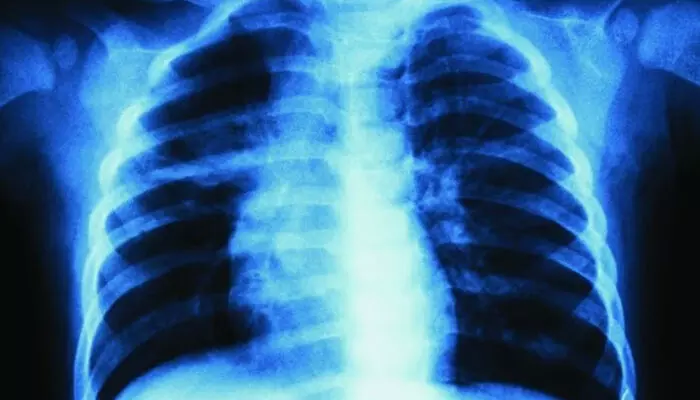

ബൈക്കില് കാറിടിച്ച് പരിക്കേറ്റു; ഇടത് നെഞ്ചില് വേദനയുണ്ടെന്ന് യുവാവ്; എക്സ്റെയെടുത്തത് വലത് ഭാഗത്ത്; കുഴപ്പമൊന്നുമില്ലെന്ന് ഡോക്ടര്; ആലപ്പുഴ മെഡിക്കല് കോളജിലും ചികിത്സാപ്പിഴവ്

അമ്പലപ്പുഴ: ആലപ്പുഴ മെഡിക്കല് കോളജിലും ചികിത്സാപ്പിഴവ് ഉണ്ടായതായി പരാതി. വാഹനാപകടത്തില് പരിക്കേറ്റ് ആലപ്പുഴ മെഡിക്കല് കോളജ് ആശുപത്രിയിലെത്തിച്ച യുവാവിന്റെ ഇടത് നെഞ്ചിന് പകരം വലതു നെഞ്ചിന്റെ എക്സ്റേ എടുത്തെന്നാണ് പരാതി. എക്സ്റേ പരിശോധിച്ച ഡോക്ടര് കുഴപ്പമില്ലെന്ന് അറിയിക്കുകയും ചെയ്തു.

പായല്ക്കുളങ്ങരയില് വെച്ച് ബൈക്കില് കാറിടിച്ചാണ് യുവാവിന് പരിക്കേറ്റത്. നെഞ്ചിനും കാലിനും പരിക്കേറ്റ യുവാവിനെ നാട്ടുകാര് മെഡിക്കല് കോളജ് ആശുപത്രിയിലെത്തിച്ചു. ഇടത് നെഞ്ചില് വേദനയുണ്ടെന്ന് അറിയിച്ചതിനെത്തുടര്ന്നാണ് ഡോക്ടര് എക്സ്റേ എടുക്കാന് നിര്ദേശിച്ചത്. എന്നാല്, എക്സ്റേ എടുത്തത് വലതു നെഞ്ചിന്റേതായിരുന്നു. പരിശോധനയില് കുഴപ്പമൊന്നുമില്ലെന്ന് ഡോക്ടര് അറിയിക്കുകയും ചെയ്ത് കയ്യൊഴിഞ്ഞു.

വേദന അസഹനീയമായതിനെത്തുടര്ന്ന് യുവാവിനെ തിരുവല്ലയിലെ സ്വകാര്യ ആശുപത്രിയിലേക്ക് മാറ്റി. ഇവിടെ നടത്തിയ പരിശോധനയിലാണ് എക്സ്റേ മാറിയ വിവരം തിരിച്ചറിഞ്ഞതും ഇടത് നെഞ്ചില് നീര്ക്കെട്ടുള്ളതായി കണ്ടെത്തിയതും. കാലിന് ഗുരുതരമായി പരിക്കേറ്റ യുവാവിനെ പിന്നീട് അടിയന്തിര ശസ്ത്രക്രിയയ്ക്ക് വിധേയനാക്കി.